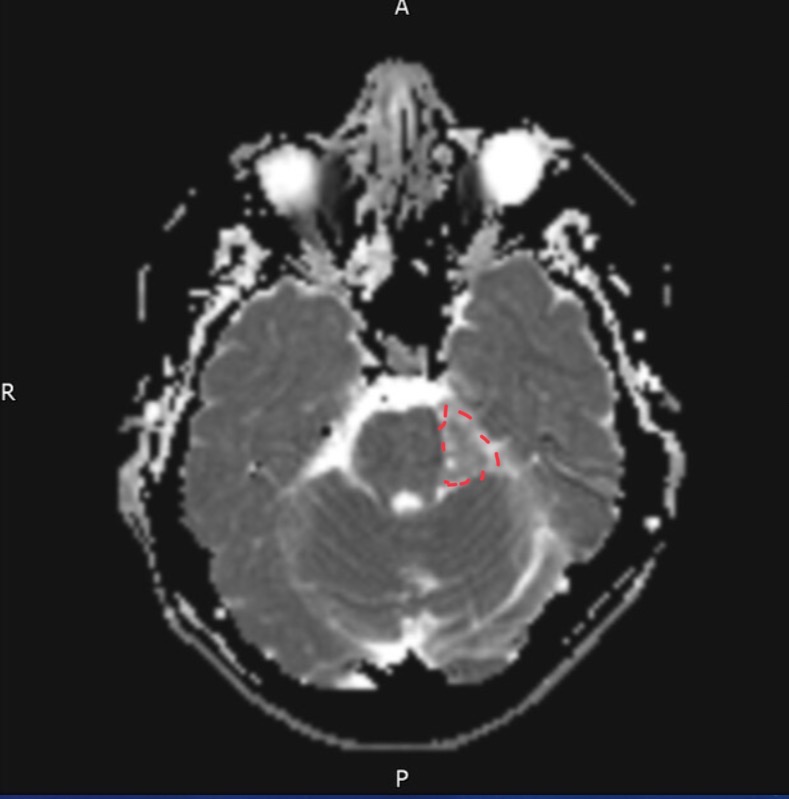

55-year-old female presents with occipital headaches and neck stiffness

Thrombosed Aneurysm of postero-inferior cerebellar artery